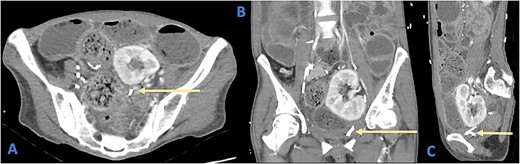

Her full blood count and biochemical analysis were relatively unremarkable with a white cell count (WCC) of 5.2 × 109/l, haemoglobin (Hb) of 100 g/l, c-reactive peptide (CRP) of 15 mg/l and arterial blood gas showing a serum lactate of 0.6 mmol/l and an acidemia with pH of 7.26. Bedside urinalysis demonstrated leucocytosis and microscopic haematuria. Computed tomography (CT) scan of her abdomen and pelvis revealed diffuse dilatation of the large bowels with a clear transition point at the rectosigmoid junction (Fig. 1). There was no evidence of viscus perforation or ischemia.

Axial (A), coronal (B), and sagittal (C) views of a CT demonstrating the position of the ureteric stent (arrows) as it crosses the rectosigmoid colon. Note the faecalization of proximal colon and dilated colonic loops.